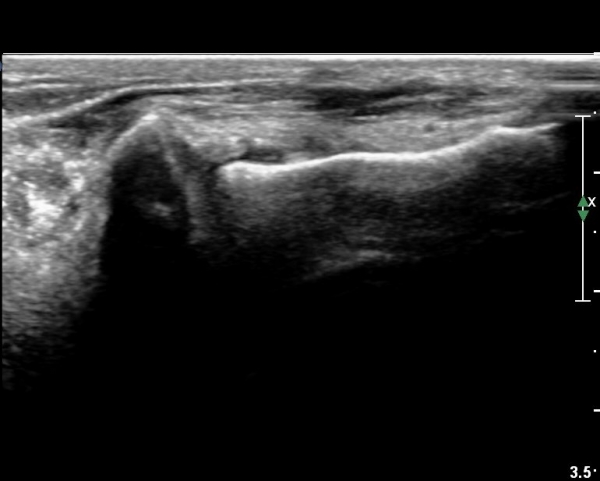

Àü°Åºñ Àδë Á¾´Ü¸é°Ë»ç¿¡¼­ Àü°ÅºñÀδëÀÇ ÆÄ¿­ÀÌ °üÂûµÇ°í(»çÁø 6,7)

ºÎÇÏ°Ë»ç ½Ã °Å°ñ°ú ºñ°ñÀÌ  °úµµÇÏ°Ô ¹ú¾îÁö´Â °ÍÀÌ °üÂûµÈ´Ù(÷ºÎµ¿¿µ»ó 2)

Á¾°ñ ÀÔ¹æ°ñ Àδë Á¾´Ü¸é°Ë»ç¿¡¼­ Á¾°ñ ÀÔ¹æ°ñ ÀÎ´ë  ÆÄ¿­ÀÌ °üÂûµÇ°í(»çÁø 6,7)

ºÎÇÏ°Ë»ç ½Ã Á¾°ñ°ú ÀÔ¹æ°ñ  °úµµÇÏ°Ô ¹ú¾îÁö´Â °ÍÀÌ °üÂûµÈ´Ù(÷ºÎµ¿¿µ»ó 3)